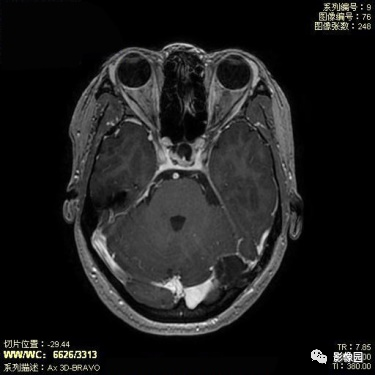

表皮样囊肿

【基本资料】患者,女,45岁

【主诉】发现颅内占位1月

【影像图片】